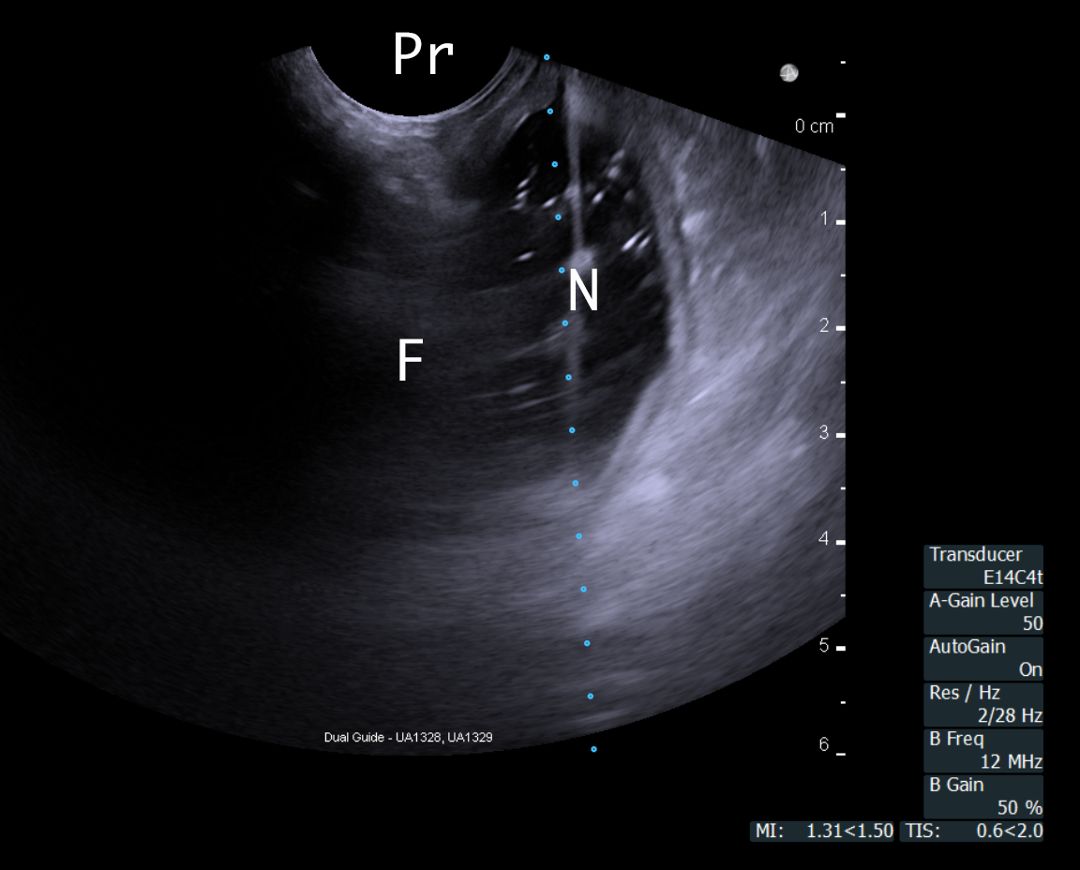

Endovaginal ultrasound-guided needle insertion of a trocar into the POD was performed in six fresh frozen female cadavers and in a live sheep animal model. Six female cadavers with the pelves intact were available for the study.  The cadavers and the ewe were placed in the dorsal lithotomy position.  Pelvic ultrasound was performed using a BK FlexFocus triplane probe.  The cul-de-sac space was identified as a fluid-filled space clear of bowel or adhesions, with visible bowel displacement with probe pressure to detect the “sliding sign” (Fig 1).  A veress needle was advanced under vaginal ultrasound guidance to confirm POD localization.  Access to the Pouch of Douglas was achieved using a blunt, extra-long metal trocar  (Fig 2).

Figure 1 Demonstrates mid-sagittal view (TVS) of Pouch of Douglas in the ewe with needle guidance line going through the free fluid.